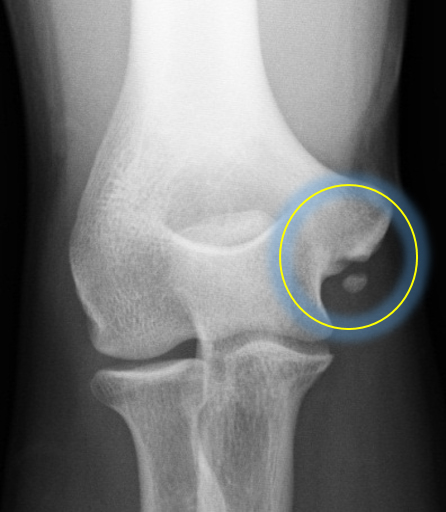

当院の調査では、内側上顆に学童期の遺残裂離骨片を有する症例(図2:リスク2.6倍),MRIでの完全損傷(図3:リスク4.6倍)を有する症例が手術を要するリスクが高まることが分かっています。詳細な評価に基づく診断を行い,3ヶ月以上のリハビリテーションを主体とした保存療法を行っても競技復帰が達成できない場合は手術療法を考慮します。手術を行う条件として,選手が競技復帰・継続を強く希望することが必須となります。

【図3 MRI検査でのUCL】